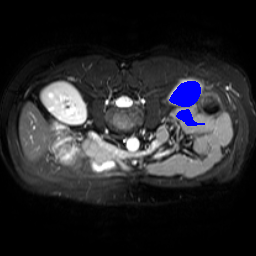

Support

Label

Proposed

In order to assess the performance of the proposed method, we compare the performance of the proposed model with excellent models in recent years. Table 1 and Table 2 shows the comparison results of different models in setting1, while Table 3 and Table 4 shows the comparison results of different models in setting2 on the data set in recent years. PANet[25] is the most widely influential few-shot model in the field of few-shot image segmentation on natural images. SENet [18] is the first few-shot segmentation model proposed for medical images. SSL-ALPNet[19] introduced the milestone of using superpixel self-supervision to train few-shot medical image models. RPNet[29] is a supervised method with a recursive mask optimization module to iteratively optimize the segmentation mask, [27] adapt it into the same self-supervision learning framework and applies setting1 to it and denoted as SSL-RPNet; CRAPNet[27] is the latest SOTA model for 2023. Compared with CRAPNet, our method outperforms most of the state-of-the-art models and only slightly outperforms CRAPNet. Figures 3 and 4 show examples of the model’s segmentation predictions on different datasets, respectively; The first row is the support map, the second row is the label map, and the third row is the segmentation prediction of the model.